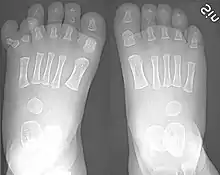

Toes

Toes on the human foot. The innermost toe (bottom-left in image), which is normally called the big toe, is the hallux.